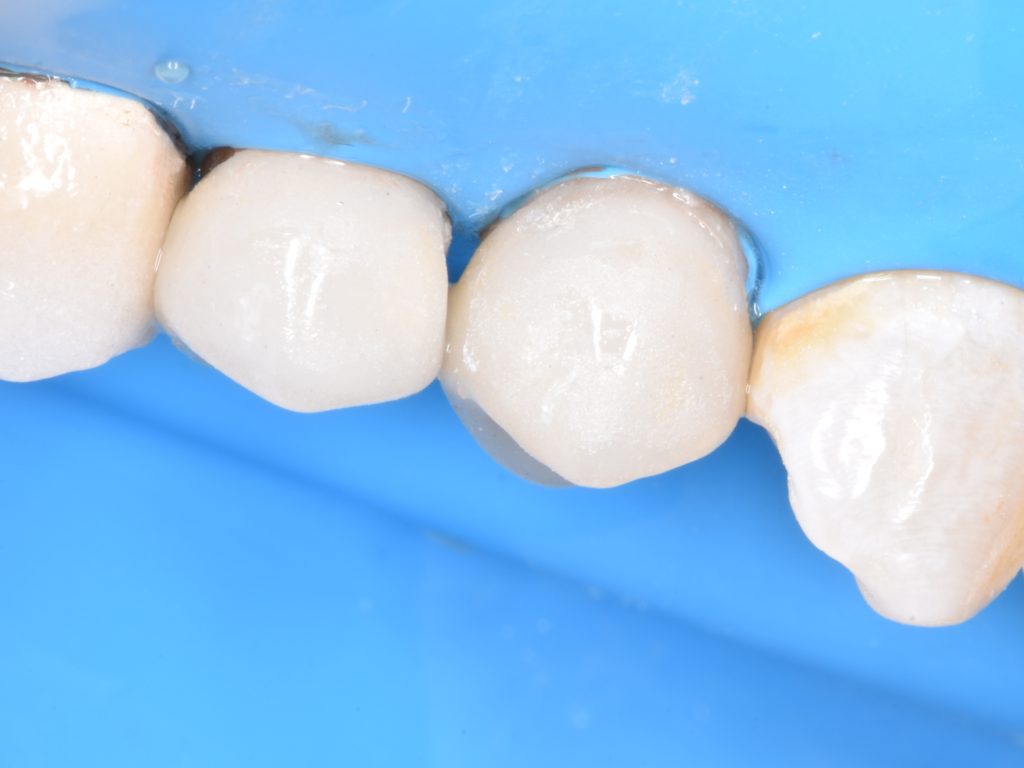

Deep margin elevation using circumferencial Copper bands

Elevation by snow plow technique n

And final design to receive to monolithic lithium disilicate restorations